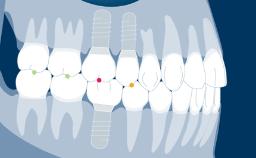

Transitional prostheses play an important role in replacing missing teeth during implant therapy, up to the point when the implants are ready to be restored.

Implant therapy often involves several clinical and laboratory stages, and transitional prostheses seek to ensure that the patient is comfortable on both an esthetic and a functional level throughout the duration of treatment.

Transitional prostheses also have important diagnostic functions, and they can be a key factor in achieving patient satisfaction with the definitive treatment outcome.

There are a number of options for transitional prostheses, both fixed and removable.